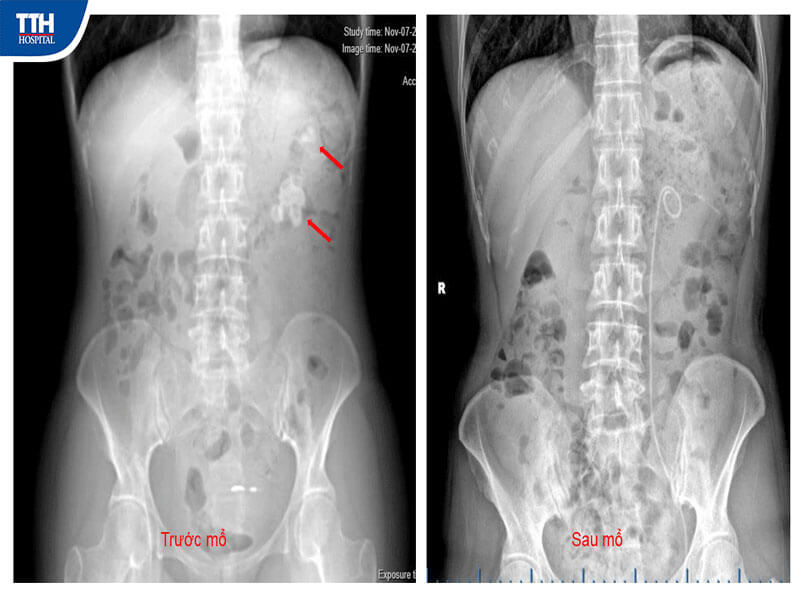

Bệnh nhân N.T.H (38 tuổi, Ba Đồn) nhập viện trong tình trạng đau hông trái kéo dài, mệt mỏi, sụt cân và lo âu nhiều ngày. Kết quả chẩn đoán hình ảnh cho thấy thận trái chứa nhiều viên sỏi kích thước lớn, phân bố ở nhiều đài thận, trong đó có những viên nằm sâu, vị trí khuất, rất khó tiếp cận bằng các phương pháp thường quy. Mong muốn của bệnh nhân là loại bỏ hoàn toàn sỏi trong thời gian ngắn, càng làm cho bài toán điều trị thêm thách thức.

Kết quả sau phẫu thuật

Chỉ sau 24 giờ, bệnh nhân N.T.H phục hồi ổn định, giảm đau rõ rệt, các chỉ số sinh tồn tốt và không ghi nhận biến chứng. Hiện bệnh nhân đang tiếp tục được theo dõi và chăm sóc hậu phẫu tại Bệnh viện Đa khoa TTH Quảng Bình.